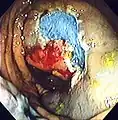

An advantage of colonoscopy over X-ray imaging or other less invasive tests is the ability to perform therapeutic interventions during the test. A polyp is a growth of excess of tissue that can develop into cancer. If a polyp is found, for example, it can be removed by one of several techniques. A snare device can be placed around a polyp for removal. Even if the polyp is flat on the surface it can often be removed. For example, the following shows a polyp removed in stages:

Polyp is identified.

A sterile solution is injected under the polyp to lift it away from deeper tissues.

A portion of the polyp is now removed.

The polyp is fully removed.